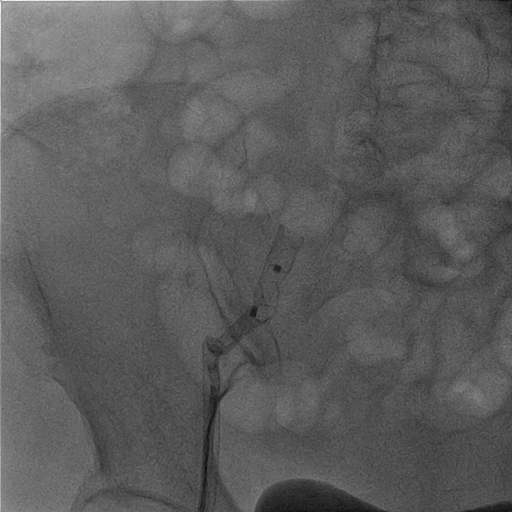

1. We made right femoral vein puncture and inserted 8 Fr sheath. Then we advanced the SL0 catheter to atrial septum.2. We used BRK transeptal needle to perform transeptal puncture under TEE guidance and advanced the dilator and SL0 catheter.3. The LAAO size was chosen under TEE and under angiography and we selected the 20/26 mm Lambre LAA Closure System (Lifetech Scientific).4. We deployed the LAA occlude. But the position of the LAAO changed soonly and unstable after the deployment under angiography and TEE view. (Image 1) (Video 1) 5. The procedure was going to be closed. However, the LAAO disappeared under the TEE view and dislodged to the aortic arch at the next moment. 6. SJM 12 Fr sheath (Abbott) was inserted through right femoral artery and we chose a JR4 8 Fr. guiding catheter. We used the JR4 to crush the LAAO at first.7. Then we used the AndraSnare (Andramed) to catch the device and pulled it to the opening of the right femoral sheath.8. It was stuck at the orifice of the sheath and kinked so that we changed to larger bore Gore sheath 24F.(Image 2)9. We used Conger GW 0.035 260cm to pass through the LAAO. And then ev3 Goose Snare 10mm 4.5Fr. (Medtronic) was used to grab the wire and LAAO together. We finally made extraction of the LAAO. (Video 2)(Image3)10. The final right common femoral artery angiography showed no contrast medium extravasation.11. The second LAAO was deployed successfully by using the Watchman Pro 27mm system (Boston Scientific).(Video 3)